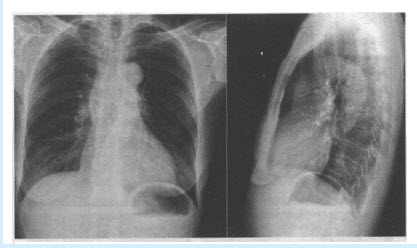

患者,男,48岁。眼睑下垂,胸痛1个月。X线平片如下图所示。

(多选题)上图X线平片所示异常包括()

A:左下肺斑片影

B:主动脉迂曲

C:膈下游离气体

D:上纵隔影增宽

E:右侧肺门影增大

F:肺动脉增宽